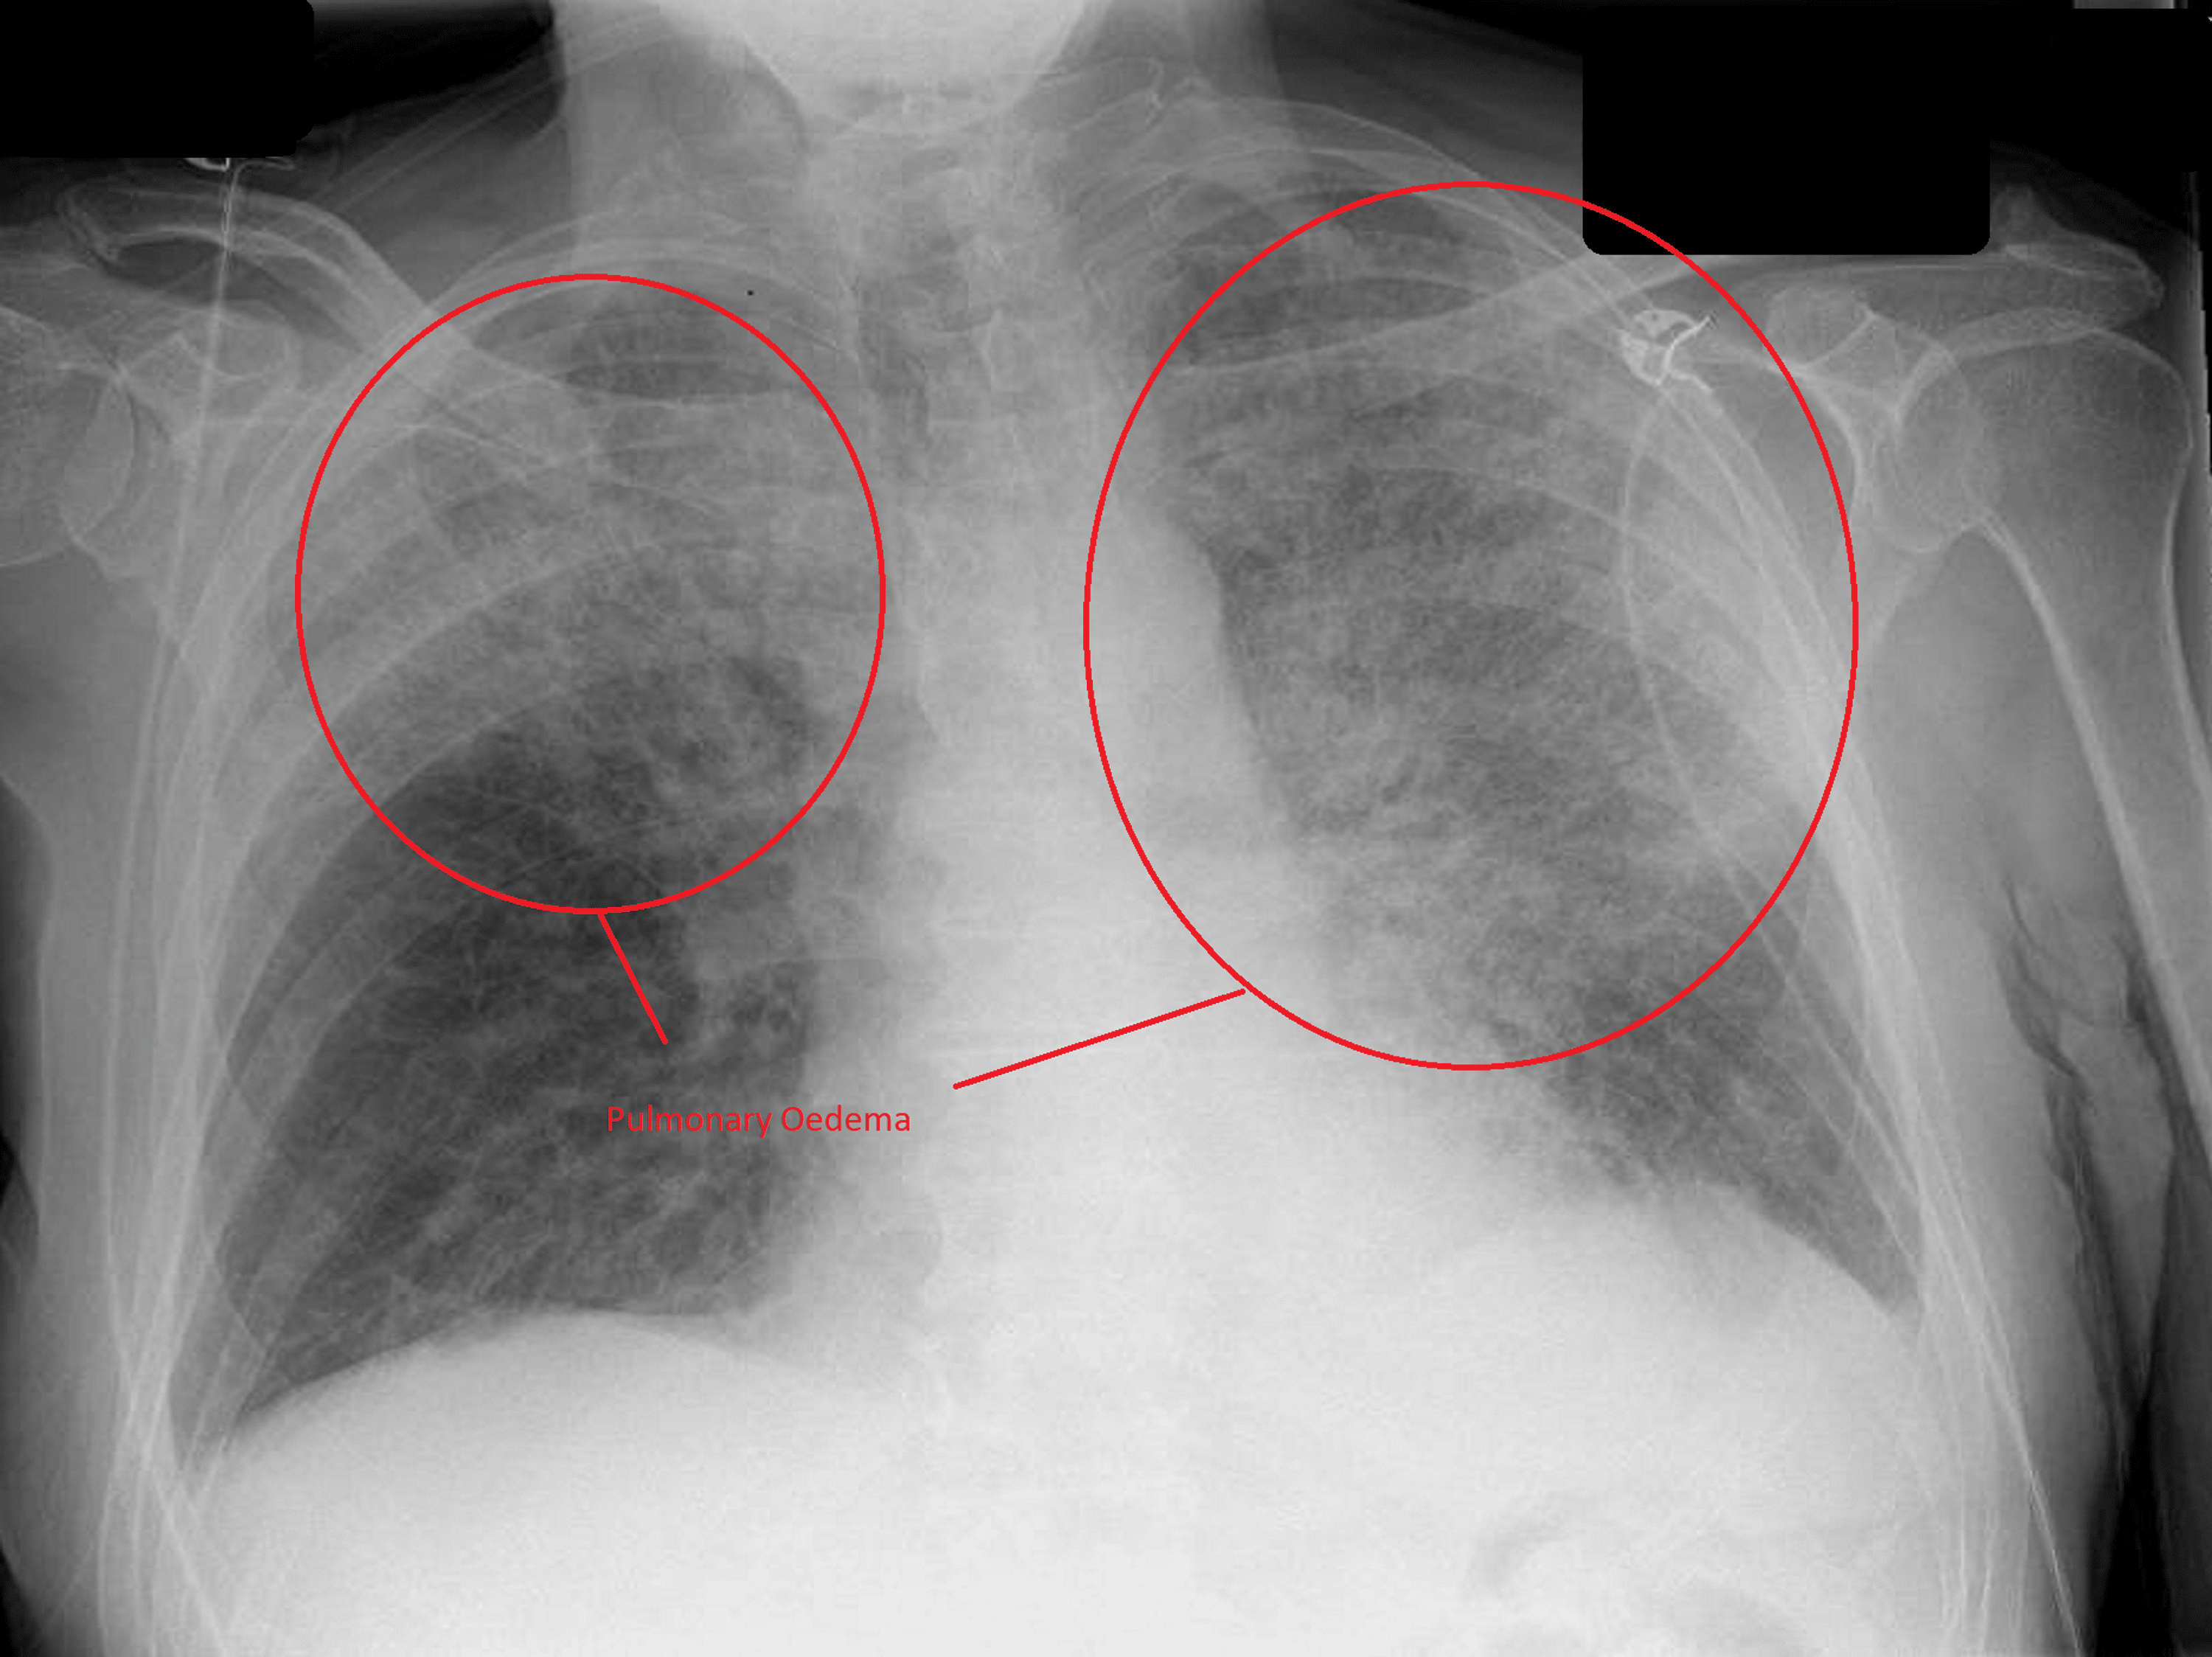

Pulmonary Edema Chest X Ray Anesthesia Pulmonary Oedema pulmonary edema increasingly is recognized as a perioperative complication affecting outcome. before making the diagnosis of negative pressure pulmonary edema (nppe), other causes of pulmonary edema must be considered, particularly those. Several risk factors have been. Postoperative pulmonary complications (ppc) are the most common medium term complications after major surgery 1 and have a. the causes of. Anesthesia Pulmonary Oedema.

Pulmonary Oedema Chest X Ray Anesthesia Pulmonary Oedema Several risk factors have been. pulmonary edema increasingly is recognized as a perioperative complication affecting outcome. negative pressure pulmonary edema (nppe) is a dangerous clinical. the causes of pulmonary oedema are cardiac failure, fluid overload, airway obstruction, acid aspiration, gas. pulmonary edema increasingly is recognized as a perioperative complication affecting outcome. Several risk factors have been.. Anesthesia Pulmonary Oedema.

Pulmonary oedema Radiology Anesthesia Pulmonary Oedema before making the diagnosis of negative pressure pulmonary edema (nppe), other causes of pulmonary edema must be considered, particularly those. Several risk factors have been. the causes of pulmonary oedema are cardiac failure, fluid overload, airway obstruction, acid aspiration, gas. pulmonary edema increasingly is recognized as a perioperative complication affecting outcome. Several risk factors have been. Postoperative. Anesthesia Pulmonary Oedema.

Pulmonary oedema Radiology at St. Vincent's University Hospital Anesthesia Pulmonary Oedema before making the diagnosis of negative pressure pulmonary edema (nppe), other causes of pulmonary edema must be considered, particularly those. negative pressure pulmonary edema (nppe) is a dangerous clinical. Several risk factors have been. pulmonary edema increasingly is recognized as a perioperative complication affecting outcome. Several risk factors have been. Postoperative pulmonary complications (ppc) are the most. Anesthesia Pulmonary Oedema.